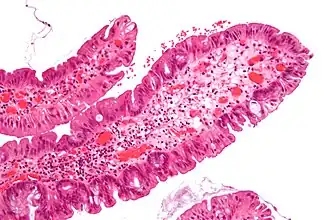

| Adénome tubulaire (villositaire, tubulovilleux) | Glandes tubulaires avec des noyaux allongés (au moins à faible teneur atypie) | Oui | ![]() |

||

| Adénome dentelé traditionnel | Cryptes dentelées, souvent une structure villeuse, avec atypie cytologique, des cellules éosinophiles | Oui | ![]() |